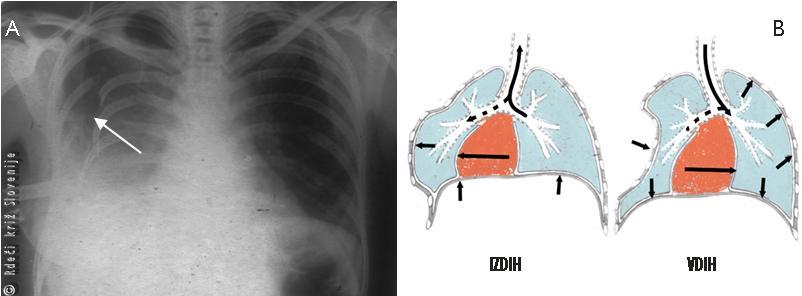

Primer 1

Na sliki je rentgenski posnetek prsnega koša mladega moškega, ki je bil zaboden z nožem v desno stran prsi. V bolnišnico je bil pripeljan 1 uro po poškodbi. Poškodovanec je bil šokiran in hipoksičen. Pri drenaži prsnega koša je priteklo 2 litra krvi. Bolnik je bil takoj operiran. Krvavel je iz interkostalne arterije in pljuč. Po operaciji je okreval brez zapletov.

Slika 6

Obsežni izliv krvi v desno prsno votlino.